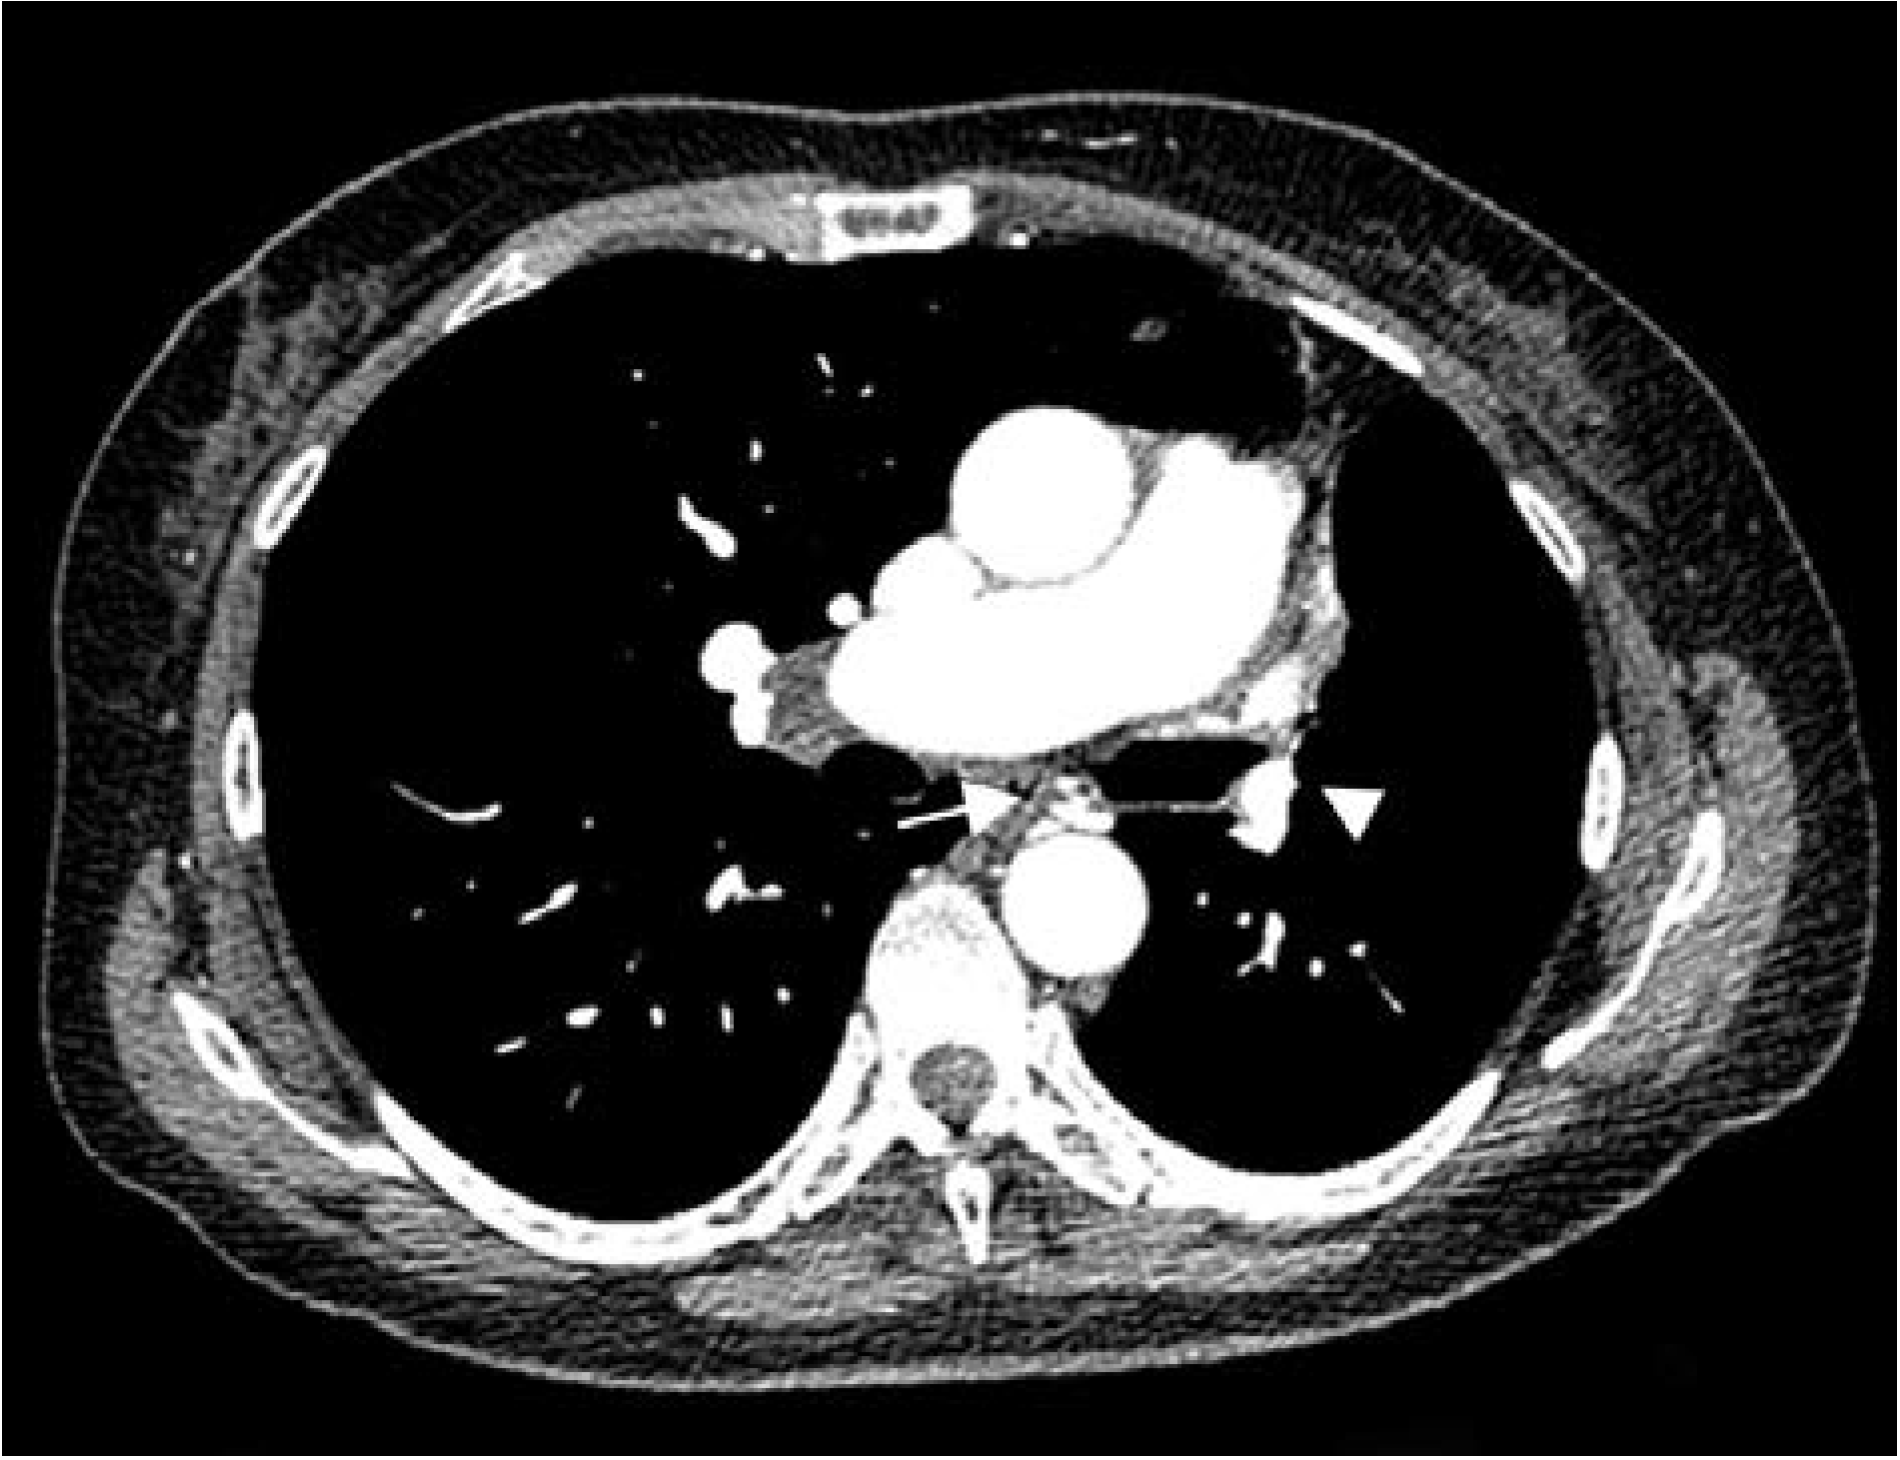

Thorax computed tomography (CT) revealed asymmetry with significantly smaller left lung. The left pulmonary artery immediately after separation was of extremely narrower lumen and so were lobar and segmental branches (Figure 2). Collaterals stemmed from mammary artery and bronchial artery (Figure 3). The results pointed towards UAPA. Subpleurally on the left, apically and basolaterally, scarred changes were noticed.

Figure 3. Computed tomography (CT) showing marked volume loss in left hemithorax, narrow left pulmonary artery (arrowhead), collateral vessel, bronchial artery (arrow).

Incidence of hemoptysis increases with age in patients with UAPA. In the study where the median patient age was 14 years the incidence of hemoptysis was 20% while in another study where the median age was 40 years, the incidence of hemoptysis was more than 40% [7,9]. In the latter study of patients with UAPA, hemoptysis was the most common symptom [9]. It is considered that the presence of significant collaterals in older patients increases the possibility of hemoptysis. The most common collaterals stem from bronchial, phrenic, mammary, intercostal arteries, subclavian artery, subdiaphragmatic branches and coronary arteries [6,9]. Hemoptysis can be self-limiting or it can be massive with fatal outcome [7]. In case of our patient, collaterals stemmed from the mammary and bronchial artery.